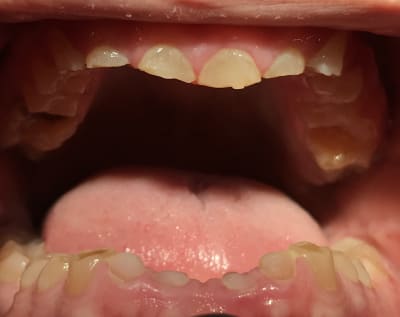

Photos

A82f03fd 2d91 4ef1 97ca f3eb47c7b10d m438gf - Eugenol

780581f7 855e 4bfa 8613 66d779c84307 rrwohx - Eugenol

poignée de porte a diagnostiqué une maladie genetique, c'est un cas d'amélogenèse imparfaite avec racines courtes, obliteration des chambres pulpaires, émail fin et de mauvaise minéralité pour du collage... necrose en lien avec l'usure (les incisives inf)

le visage est harmonieux , la dv est donc bonne .

il faudrait donc faire des élongations maousses , mais comme les racines sont courtes , ce sera des implants .

Oui Mla2 problème génétique + bruxisme. Quand vous expliquiez qu’il était camé moi je veux bien mais bon regardez ses 6 . Ses prémolaires sont quasi intacts . Ils se seraient foutus de l’acide juste sur ses incisives et ses molaires .... étrange. :)

Et oui implants sur tout le secteur antérieur + 46 et 36 avec un petit rabotage de 12 à 22. Plus couronnes sur 16 et 26 et sur d’autres pour refaire les courbes . Et pas de changement de DVO effectivement comme le montrent ses PM et ce qu’ a dit Enlaye.

L'amélogénese imparfaite, toutes les dents sont touchées à égalité; et l'émail a un aspect visuellement altéré.